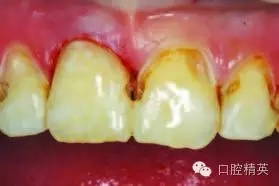

圖3:#6smartburs最先用于去除腐質(zhì)

圖4:去除大量齲壞得牙本質(zhì)后

使用#6 Smartburs II車針( SSWhite)在轉(zhuǎn)速15,000轉(zhuǎn)每分鐘下開始去腐(圖3)。使用該車針去腐至該型號的車針頭部無法進(jìn)入較小的齲壞部位有效去腐(圖4)。

接下來使用#4 Smartburs II車針完成剩下的感染牙體組織的去腐操作(圖5)。